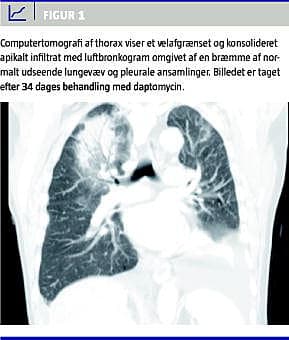

Fire uger efter påbegyndt daptomycin kom på ny CRP-stigning til over 100, og patienten udviklede dyspnø. Røntgen og computertomografi (CT) af thorax (Figur 1 ) viste et velafgrænset konsolideret apikalt infiltrat med luftbronkogram omgivet af en bræmme af normalt udseende lungevæv og pleurale ansamlinger. På mistanke om atypisk pneumoni erstattedes ceftriaxon med ciprofloxacin og rifampicin. To dage herefter seponeres daptomycin som planlagt efter i alt fem ugers behandling (Figur 2 ). Legionella - og pneumokokantigen i urin (LUT og PUT) samt bloddyrkning var negative. Man fortsatte dog behandlingen for mistænkt atypisk pneumoni. Patien-ten fik det bedre, og CRP faldt fra 105 til 18 i løbet af 14 dage. Bronkioalveolær lavage (BAL), der blev foretaget fire dage efter seponering af daptomycin og seks dage efter opstart med ciprofloxacin og rifampicin, viste normale makroskopiske forhold. De mikrobiologiske og patologiske undersøgelser af bronkialsekretet og børstebiopsi viste ingen mykobakterier, cancer eller eosinofile celler. Der blev desværre ikke udført undersøgelse for atypisk pneumoni på bronkialsekretet. Kontrolrøntgen tre uger efter seponering af daptomycin viste, at lungeforandringerne var svundet. Under hele forløbet var serumleukocytter og -eosinofilocytter i normalområdet.